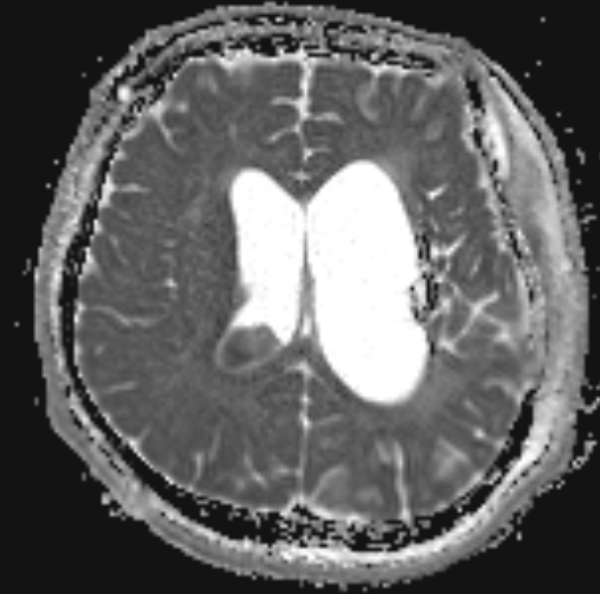

9.MRI에서 나타나는 대표소견 아래와 같이 나타남.

FLAIR : intraventricular debris layering

T1 contrast : ependymal enhancement

DWI : restricted diffusion (pus)

Hydrocephalus

5.세균 + 면역세포 + 단백질 + necrotic cell들이 쌓여 덩어리를 생성함. MRI FLAIR에서 저류층이 관찰됨.

Debris가 CSF 흐름 통로를 막아 급성폐색수두증을 발생시키며, ICP 상승으로 Cushing triad 관찰됨.